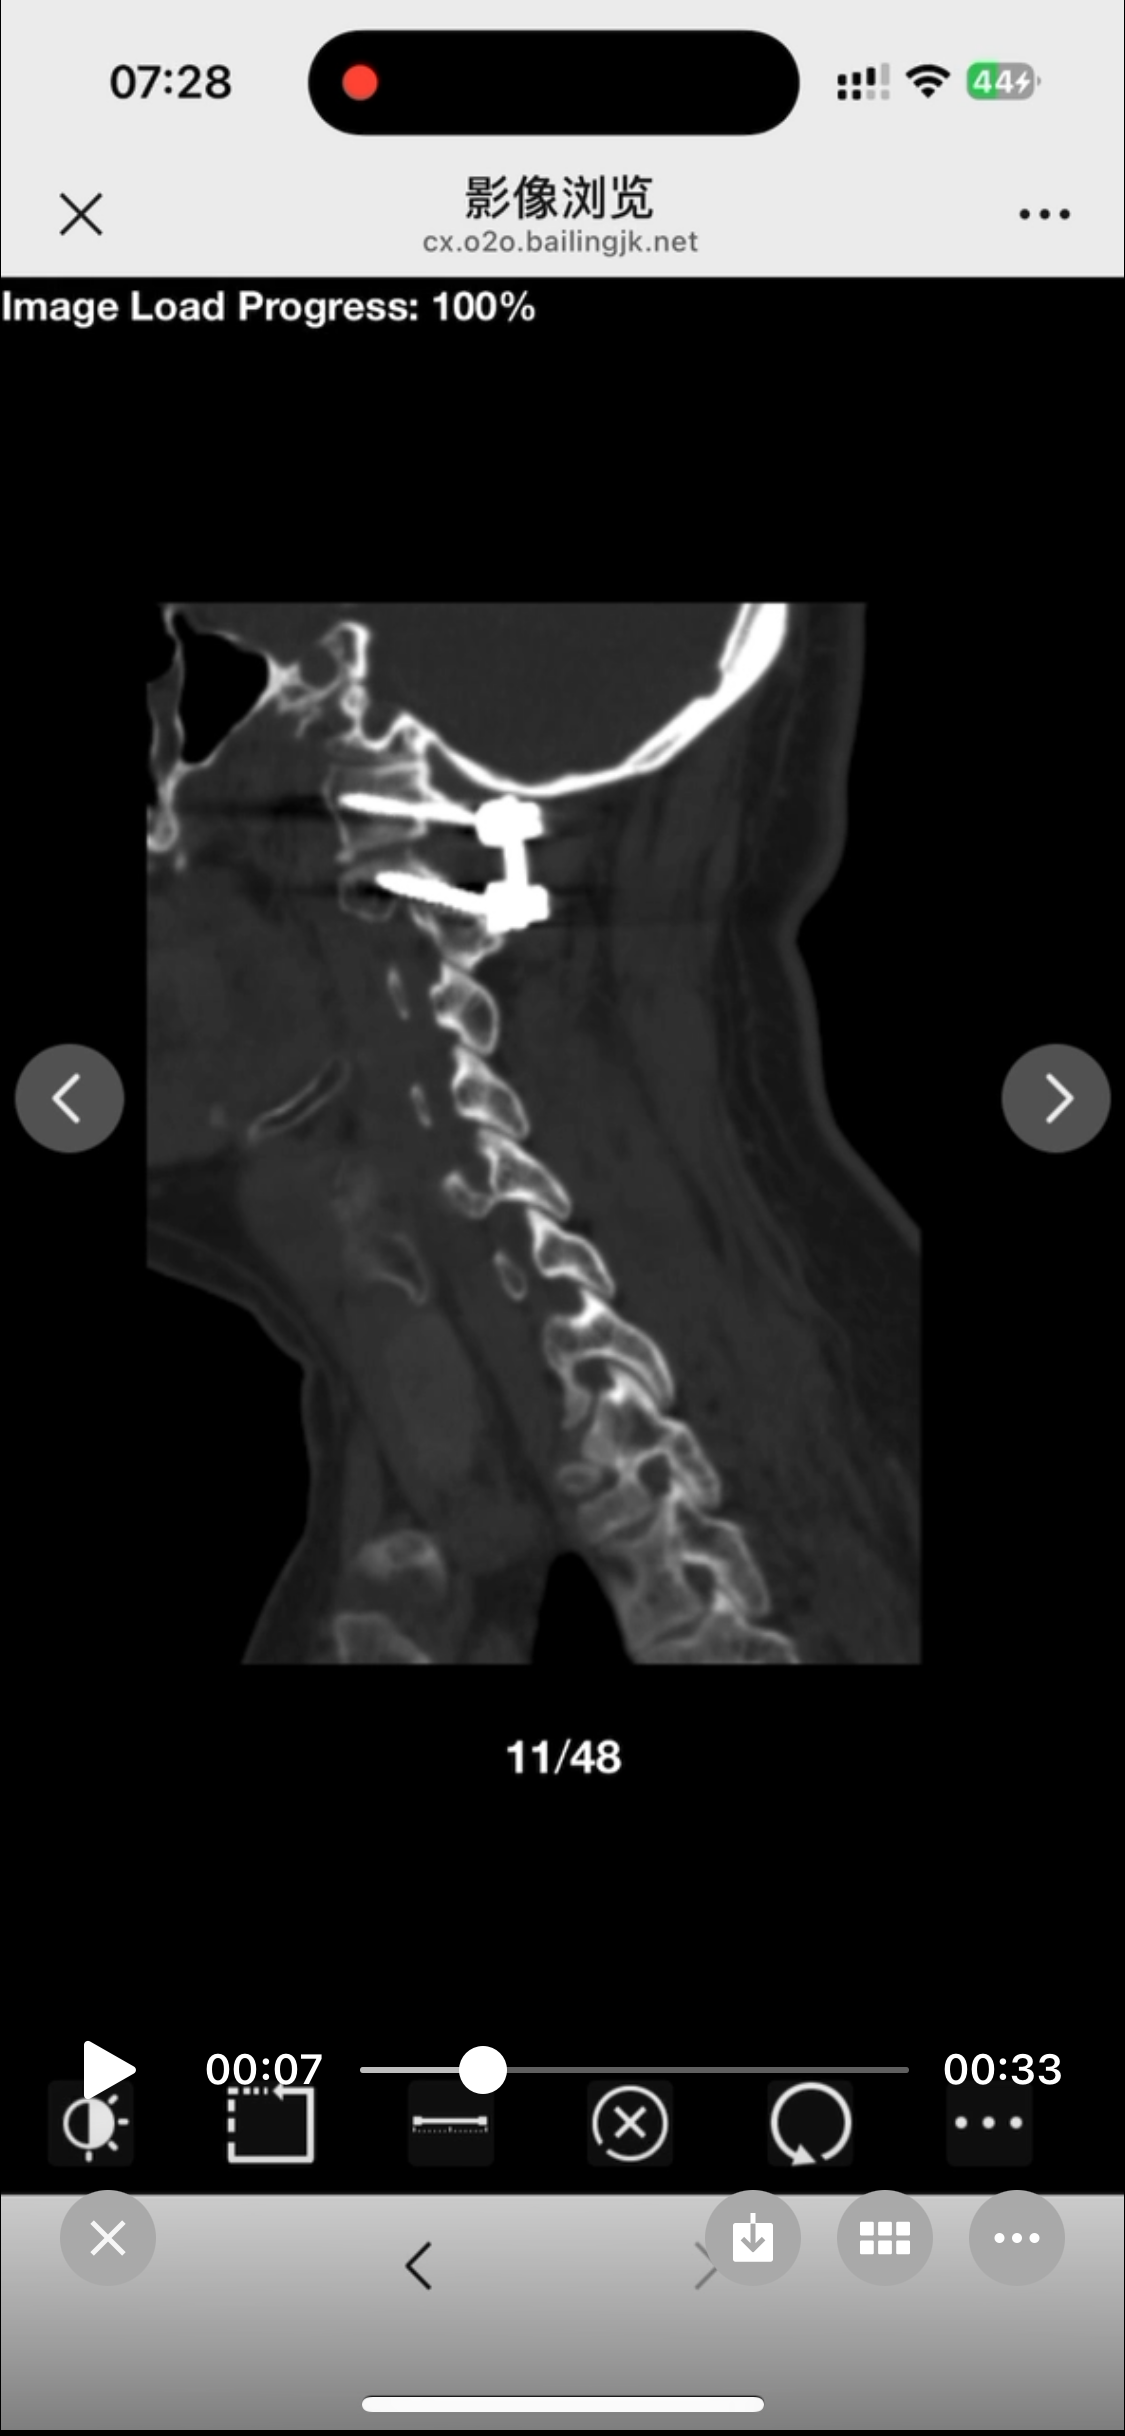

• 诊断:寰枢椎脱位

• 日期:2024.10.11

• 医院:宣武医院

• 主刀:关键

• 术后状况:术前患者同意不放融合器,术中切了后宫,术后复位还不错

• 术后影像: